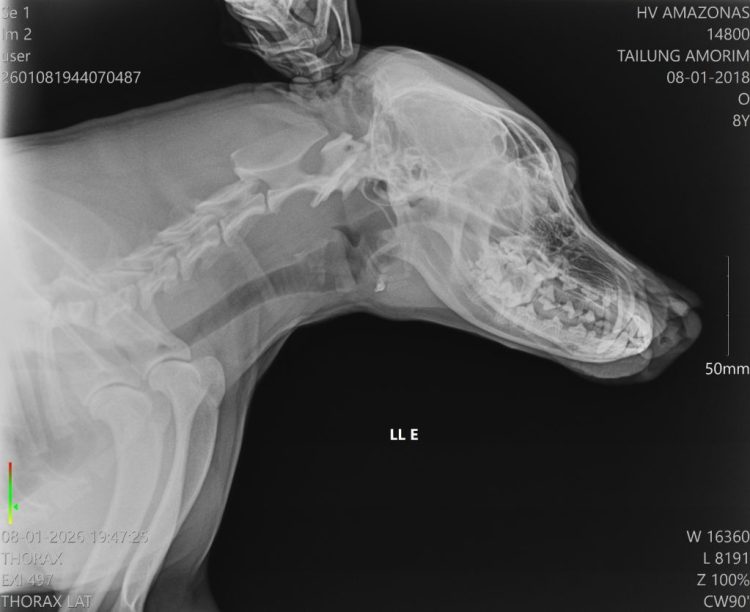

A Secretaria de Estado de Proteção Animal (Sepet) socorreu, na noite de quinta-feira (8/01), um cachorro vítima de agressão na comunidade Nossa Senhora do Livramento, localizada no igarapé do Tarumã-Mirim, à margem esquerda do Baixo Rio Negro, zona oeste de Manaus. O animal sofreu um golpe de terçado no focinho e foi encaminhado para atendimento no Hospital Público Veterinário do Amazonas (HPVet-AM).

Após ser vítima de maus-tratos, o animal foi levado pelo tutor de forma segura até a unidade hospitalar. No local, recebeu atendimento de médicos-veterinários, passou por avaliação clínica e está em tratamento intensivo para a recuperação do ferimento.

De acordo com a equipe hospitalar, o cachorro apresentava uma lesão profunda na região do focinho, mas estava consciente e respondeu bem ao atendimento. A cirurgia foi bem-sucedida e o animal já foi encaminhado para casa, onde permanecerá em observação pelo tutor, além de seguir acompanhado pela equipe multidisciplinar do HPVet-AM.